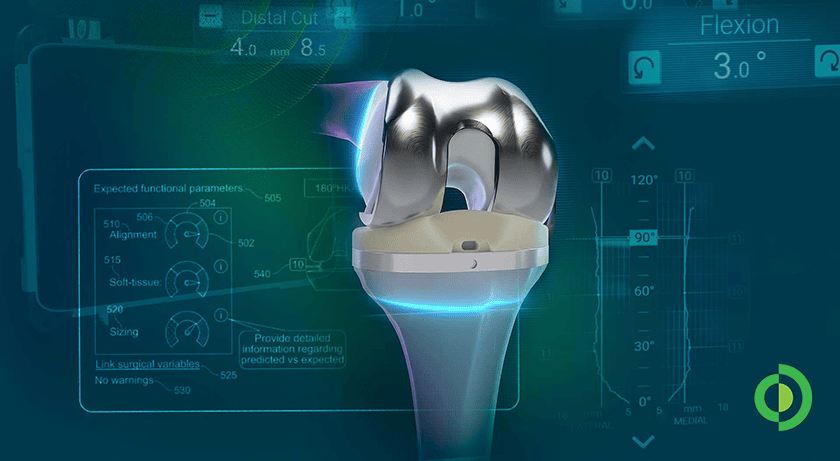

Hubly Surgical received FDA 510(k) clearance expanding Hubly Auto-Stop Drill indications to include spinal decompression procedures. In neurosurgical applications, the device’s SMART auto-stop halts rotation and prevents forward plunge at the instant of skull penetration, preventing over-drilling into patients’ brains. The new clearance expands use to laminectomy and laminotomy for spinal decompression to drill through the vertebral lamina and protect patients from damage to the spinal cord.

Hubly Surgical received FDA 510(k) clearance expanding Hubly Auto-Stop Drill indications to include spinal decompression procedures. In neurosurgical applications, the device’s SMART auto-stop halts rotation and prevents forward plunge at the instant of skull penetration, preventing over-drilling into patients’ brains. The new clearance expands use to laminectomy and laminotomy for spinal decompression to drill through the vertebral lamina and protect patients from damage to the spinal cord.